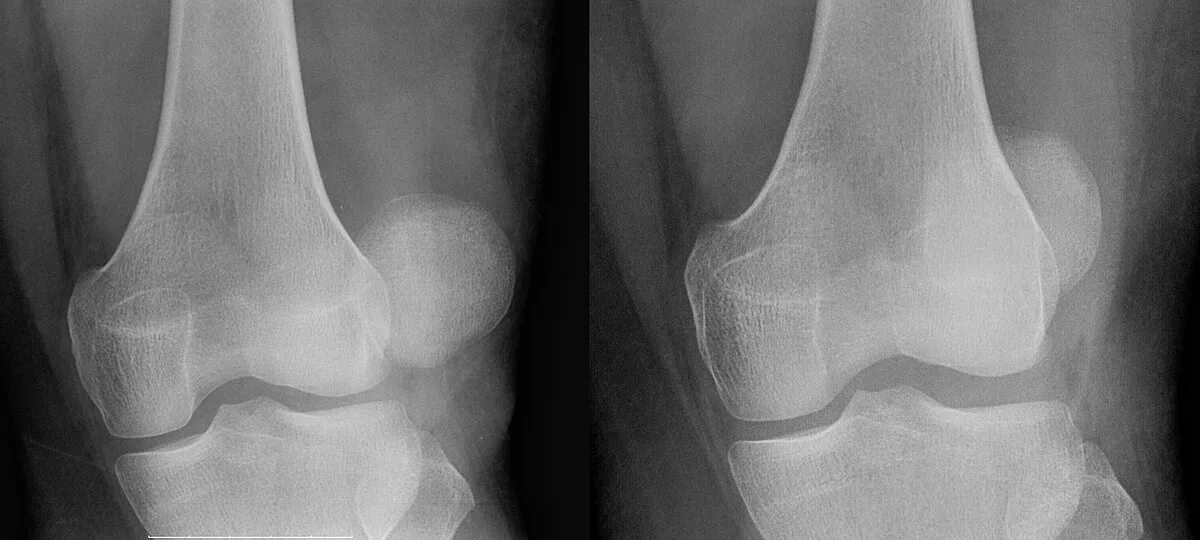

Перелом надколенника код по мкб 10